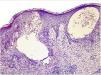

Ante la sospecha diagnóstica, se decidió la realización de biopsia. Se obtuvieron 2 fragmentos de piel para estudio con hematoxilina y eosina e inmunofluorescencia directa (IFD). En la biopsia se observó una epidermis ortoqueratósica con acantosis irregular, marcada exocitosis de eosinófilos y presencia de espongiosis con formación de vesículas espongióticas, La dermis superficial y media mostraba una dermatitis perivascular compuesta de un infiltrado mixto, de predominio linfocitario con abundantes eosinófilos (fig. 2).